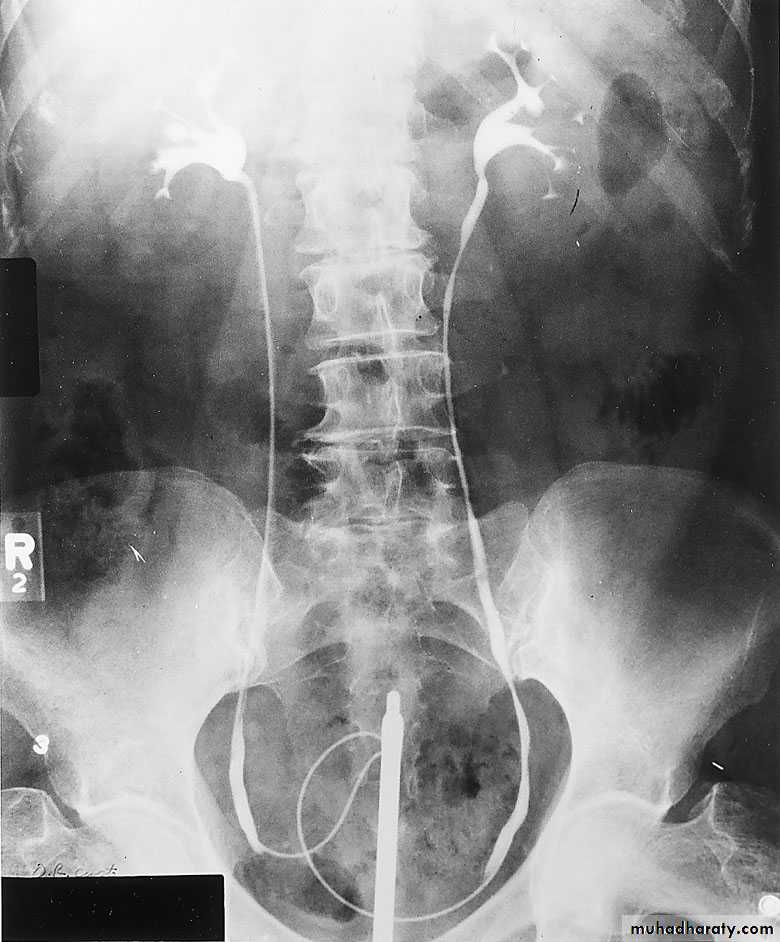

IVU needs Patient PreparationRETROGRADE PYELOGRAPHY

Opacification of the ureter and pelvicalyceal system by the retrograde injection of contrast media using ureteric catheter.Indications

Employed after an excretory urogram that inadequately visualized the anatomy of the upper tract.when there are contraindications to do IVU

Retrograde ureterogram demonstrating the collectingsystem with radiolucent filling defect in the renal pelvis.